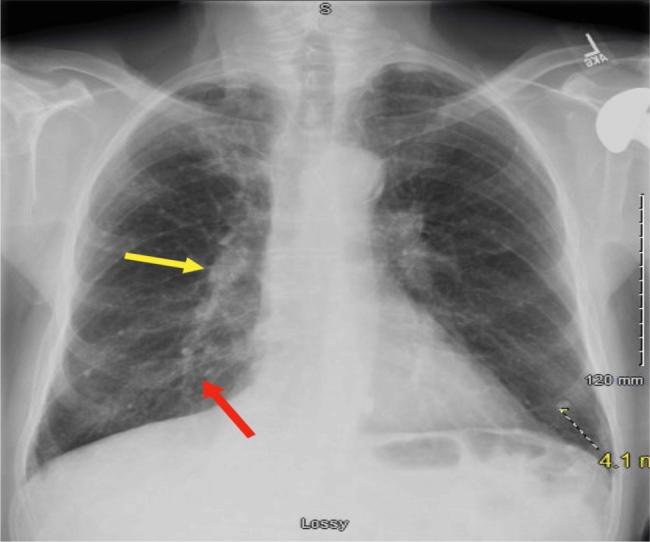

We present a case of a 78-year-old male with CLL receiving chemotherapy, who developed burning pain in the tongue and oral mucosa, accompanied by a non-productive cough. He was initially diagnosed with pneumonia, but further investigation revealed co-infection involving and .

The coexistence of and underscores the complexity of infectious complications in CLL. The patient's chemotherapy was halted due to active pneumonitis observed on imaging in order to improve his leukocyte count. Antifungal therapy was not initiated due to a lack of evidence of invasive fungal infection. Antimycobacterial therapy for complex was initiated.

我们报告一例78岁接受化疗的CLL男性患者,他出现舌部和口腔黏膜灼痛,并伴有干咳。他最初被诊断为肺炎,但进一步检查发现同时感染了两种病原体。

两种病原体的共存强调了CLL感染并发症的复杂性。由于影像学检查发现活动性肺炎,为了提高白细胞计数,患者的化疗被暂停。由于缺乏侵袭性真菌感染的证据,未开始抗真菌治疗。开始了针对复杂分枝杆菌感染的抗分枝杆菌治疗。